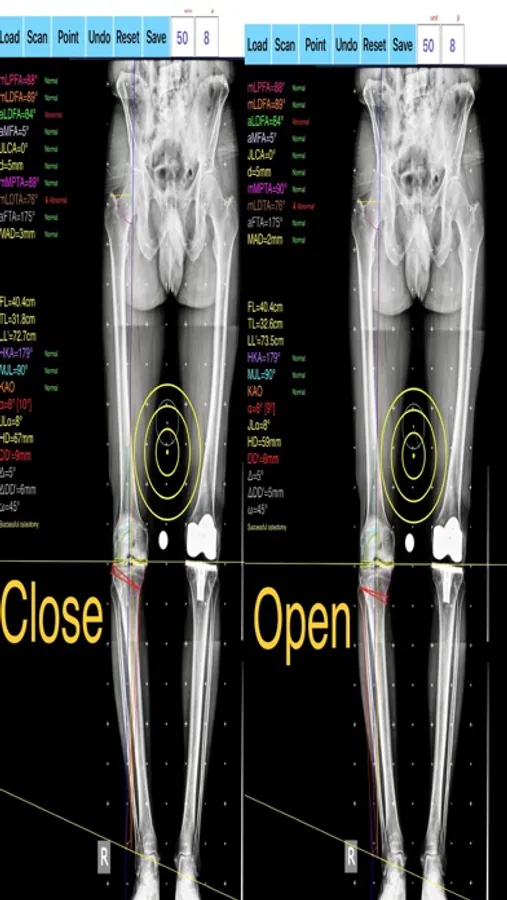

-the amount of correction preoperatively by calculating the dimension of wedge size , the correction angle and osteotomy gap opening or closing.

-mechanical axis deviation (in mm) MAD, anatomical and mechanical femoral axes angle (aMFA),mechanical lateral proximal femoral angle (mLPFA), mechanical lateral distal femoral angle(mLDFA), joint line convergence angle (JLCA),mechanical medial proximal tibial angle (mMPTA), Mechanical lateral distal tibial angle (mLDTA), Hip Knee Ankle line (HKA) ,Mid joint line (MJL) orientation.

-objectively the deviation or deformity in the frontal plane (varus or valgus) and differentiate the level of deformity (femoral and or tibial origin) and according to measured angles objectively suggest where indicated, medial or lateral, open or closed-wedge distal femur osteotomy or high-tibial osteotomy or double osteotomies and avoiding unwanted obliquity of the joint line

-evaluate in real time the success of intended osteotomy by evaluating the kinematic alignment of the knee (KAO), avoiding residual joint obliquity or malalignment.

-measure the correction angle adjusted due to ligament instability and preoperatively calculate the height of osteotomy gap opening.

-pressing + or - button, one degree of correction is added or subtracted respectively and the second plane of osteotomy emerges and printed in screen real offering real time simulation of the wedge osteotomy in an instant to comprehend in real time what parameters are affected and modify favourably the correction angle. All above mentioned angles and all limp axes are redrawn and updated accordingly for the given new correction angle. The drawn schematic gives the impression of settings act as a whole interchangable interacting unit.

OsteotomyApp Screenshots